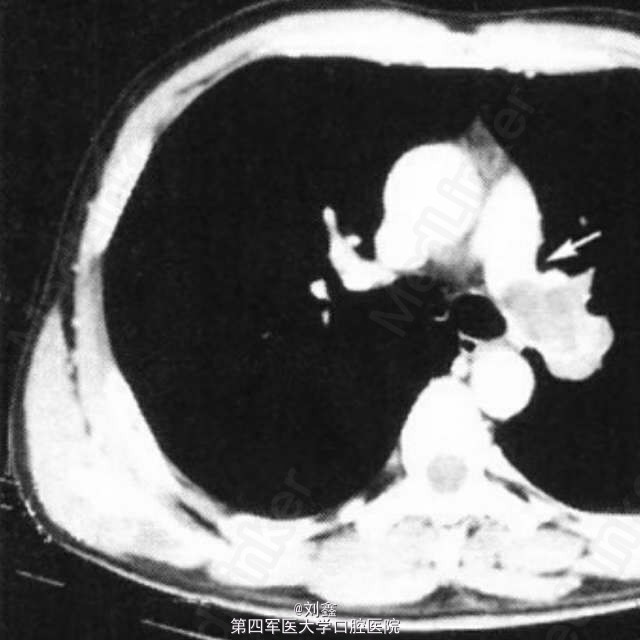

患者男,38 岁。因刺激性咳嗽 2 月余入院。既往体健,无手术史,吸烟史 20 年,15 支/d。CT 检查示,左肺根部肿物,包绕左肺动脉干,并突入左肺动脉干内,考虑左肺中央型肺癌 (图 1)。入院后检查未见远处转移,行左侧开胸探查。 术中发现左肺门左肺动脉干处大块肿物,大小约为 4.2 cm×3.8 cm,包绕左肺动脉干。游离左肺动脉干,可触及左肺动脉干内肿块,质地较硬,仍考虑中央型肺癌侵及肺动脉。术中决定行左全肺切除,依次切断左肺上下静脉及左主支气管,以血管闭合器闭合左肺动脉干,切除左全肺,清扫淋巴结。术后大体标本示,肺动脉干内球形肿物,表面光滑。病理检查示,左肺动脉干平滑肌肉瘤。免疫组化结果示,肿瘤起源于肺动脉平滑肌细胞。术后患者恢复良好,但拒绝行放化疗及其他治疗,于术后 9 个月死于远处转移。